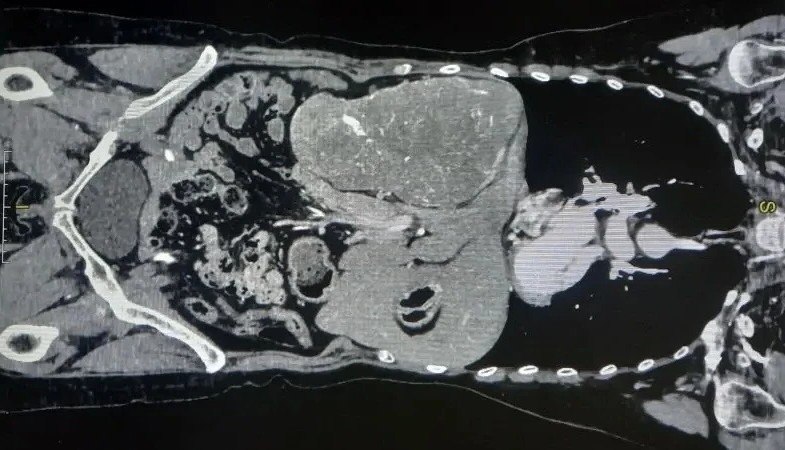

Опухоль почки размером с дыню сместила печень пациентки влево

Волгоградские врачи столкнулись с необычным случаем. У пациентки обнаружили опухоль почки размером с небольшую дыню. Гигантское новообразование фактически вытеснило жизненно важные органы с их привычных мест. Опухоль выдавила печень пациентки из правой части брюшной полости в левую. Хирурги областного онкодиспансера провели уникальную операцию женщине с редкой анатомией.